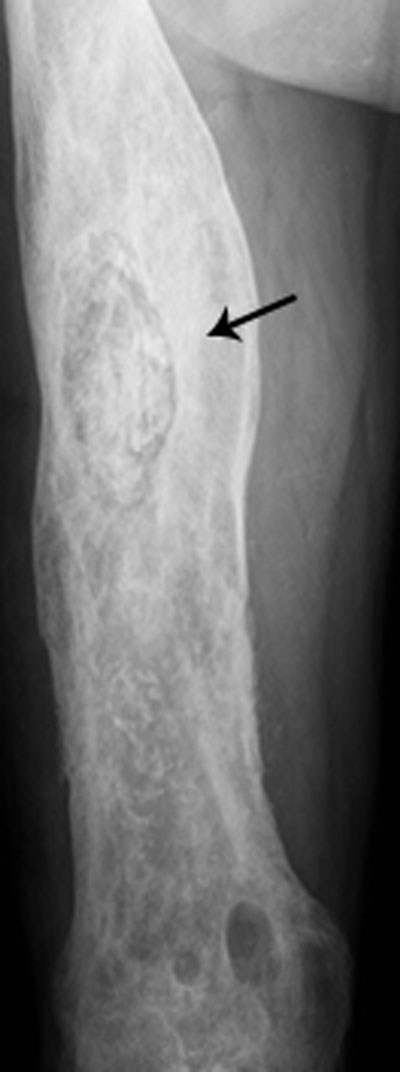

Figure 11

Chronic osteomyelitis on plain radiograph of the femur. Plain radiograph shows diffuse inhomogeneous osteosclerosis of the right femur with a focal area of increased opacity representing necrotic bone or sequestrum (black arrow). Plain films are often difficult to interpret because of superposition of viable and necrotic bone each with a different radiopacity.